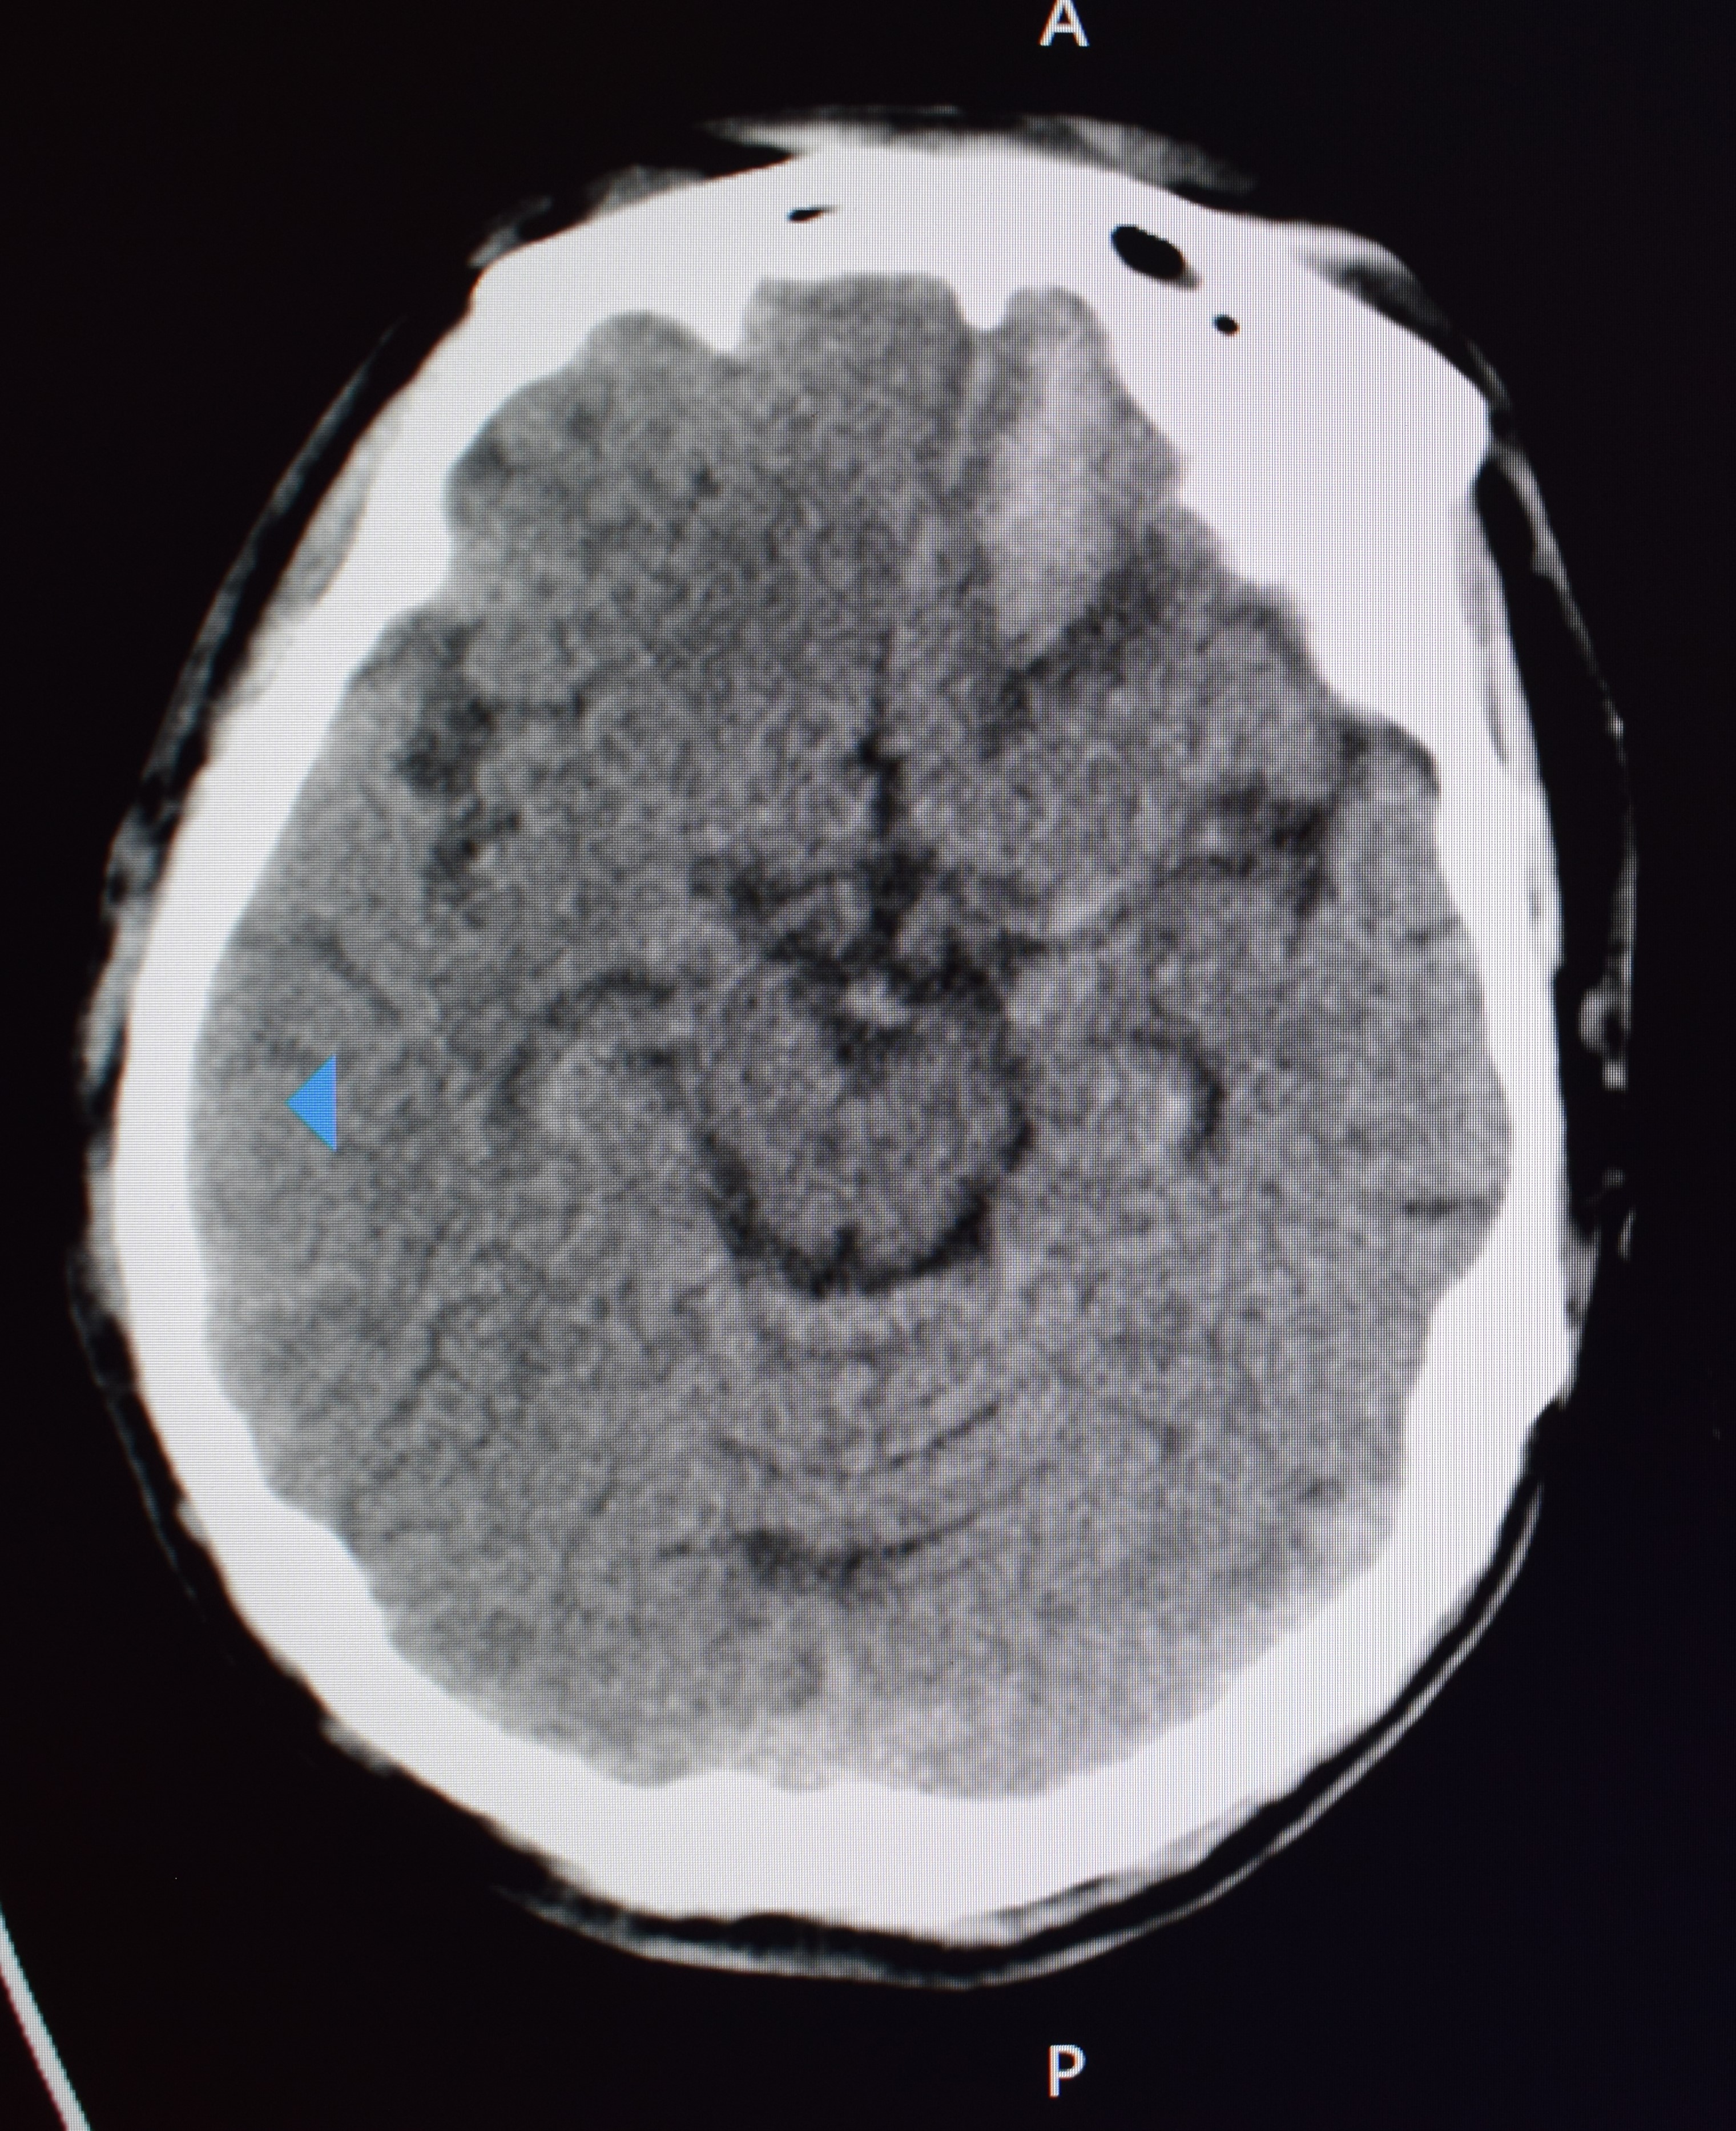

患者在外院治疗期间仍反复发热,体温最高值38.8 ℃,左眼睑肿胀加重,可见分泌物溢出。遂于8月31日就诊于急诊科,多学科会诊考虑鼻眶真菌感染,脑内多发栓塞可能性大,不排除左侧额叶病变感染可能,建议应用美罗培南、万古霉素,继续口服泊沙康唑治疗,应用左氧氟沙星及那他霉素滴眼液滴眼。遵会诊意见用药。9月8日复查颅脑CT示脑出血(见图 5)。再次组织多学科会诊,修正诊断:(1)鼻-眶-脑毛霉菌病;(2)急性脑梗死;(3)急性脑出血;(4)糖尿病。

|

| 颅脑CT示左侧额叶脑出血 图 5 患者9月8日颅脑CT |